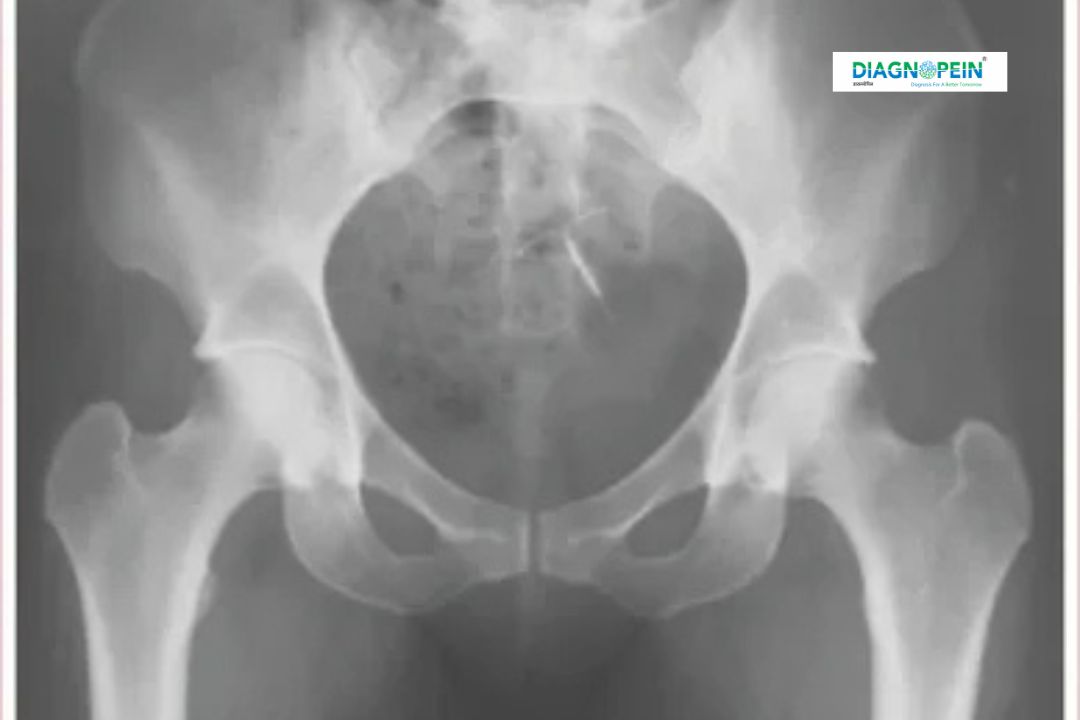

X-RAY SACRUM AP/LAT is a specialized radiographic imaging test used to evaluate the sacrum, the triangular bone located at the base of the spine between the hip bones. This test includes Anteroposterior (AP) and Lateral (LAT) views, allowing doctors to clearly assess the alignment, structure, and integrity of the sacral region.

At Diagnopein Diagnostic Center in Nashik, X-RAY SACRUM AP/LAT is performed using advanced digital imaging systems that provide clear, high-resolution images with minimal radiation exposure. This test plays a vital role in diagnosing injuries, degenerative changes, infections, congenital abnormalities, and inflammatory conditions affecting the lower spine and pelvic region.